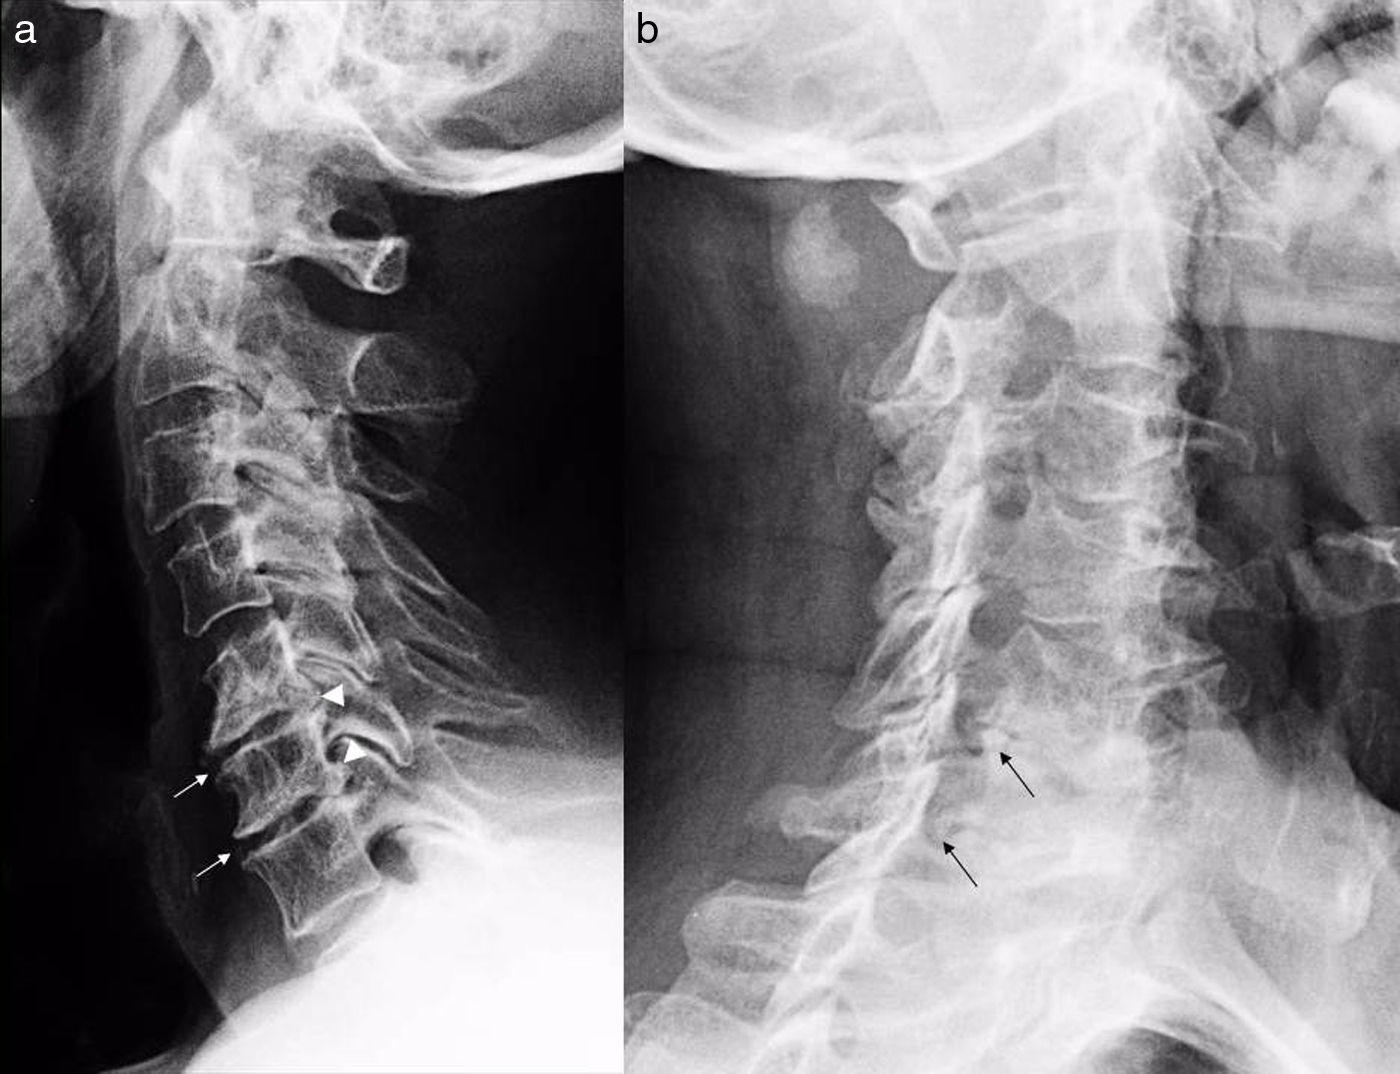

La columna vertebral es una estructura ósea que se compone de 33 vértebras superpuestas las unas sobre las otras.

Ésta protege a la médula espinal y soporta la cabeza y el tronco.

Por lo que no hay ningún tipo de vida posible sin este órgano vital del cuerpo humano, ya que es el que alberga la mayor parte del sistema nervioso central que desciende a lo largo del canal vertebral.

La columna vertebral se compone de 33 huesos apilados los unos sobre los otros.

La columna vertebral da el apoyo principal a tu cuerpo, te permite estar de pie, doblarte, girarte y protege a la espina dorsal de las lesiones.

Los músculos, los huesos sólidos, tendones, ligamentos flexibles y los nervios hacen que la columna vertebral se mantenga sana.

Sin embargo es una de las estructuras que se ve más afectada en un accidente, una lesión o una enfermedad que puede causar fuertes dolores.